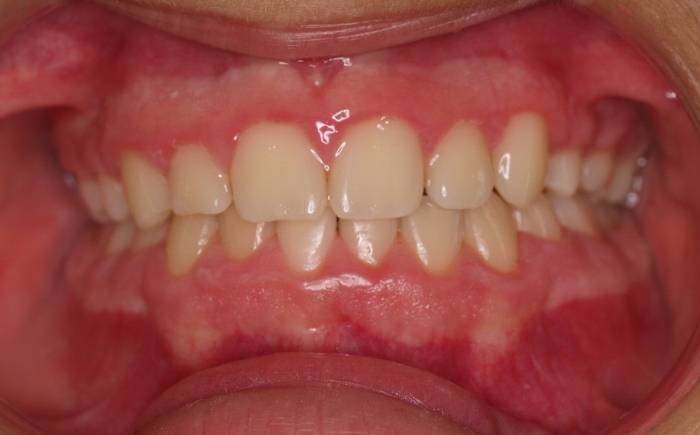

Fotos antes tratamiento:

El paciente M.C. acude a nuestra consulta por:

– Apiñamiento importante

– Perfil convexo

– Forma arcada estrecha

-sobremordida

Con lo que decide realizarse un tratamiento de ortodoncia de duración de 26 meses con brackets smartclip 022 de acero.